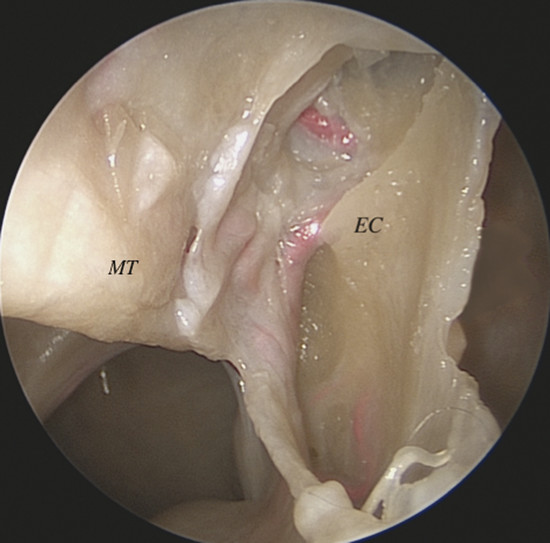

It gives off two main branches, the posterior lateral nasal artery (PLNA) and the posterior septal artery (PSA), 1 , 2 which can be divided into one or two trunks medial to the ethmoidal crest, before or after crossing the sphenopalatine foramen. It is rarely possible to identify more than two trunks. 1 , 3 The PLNA supplies the region of the lateral nasal wall giving off branches to the inferior turbinate (inferior turbinate artery), middle turbinate (middle turbinate artery), mucosa of the fontanelle, and to the mucosa of the maxillary sinus 4 (Fig. 3‑3, Fig. 3‑4). In approximately 20% of cases this artery supplies the superior turbinate. 5 The inferior turbinate artery enters a bony canal and runs anteriorly along the turbinate. It usually gives off two terminal branches, within or adjacent to the bone, supplying the mucosa of the turbinate (Fig. 3‑5). The artery gives off several small vessels to the maxillary sinus and to the ethmoidal complex. The middle turbinate artery gives off several branches, some of which run along the medial surface of the turbinate whereas the other branches supply the lateral turbinate surface and anterior ethmoidal complex (see Fig. 3‑3).